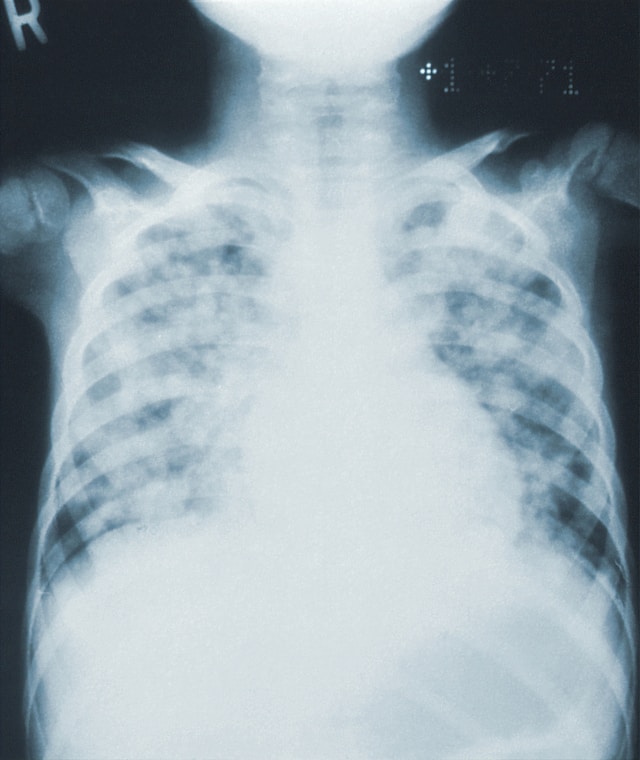

Photo by CDC on Unsplash